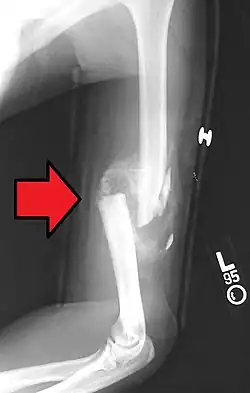

A transverse fracture of the humerus shaft -

A displaced supracondylar fracture in a child